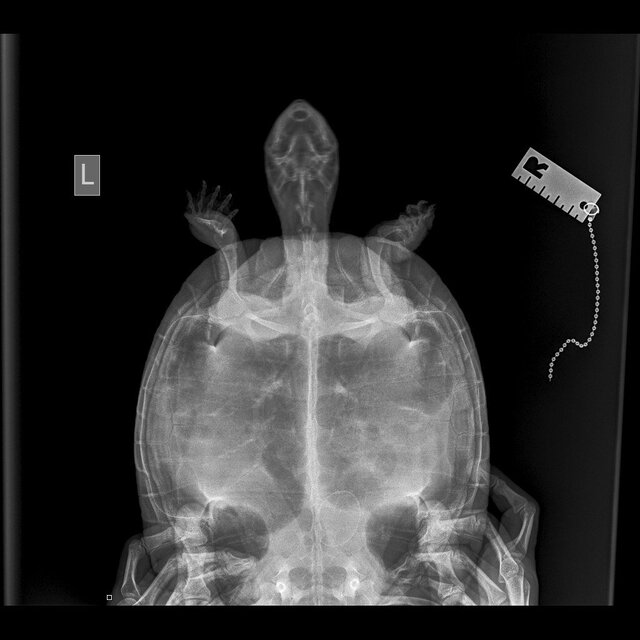

@moth , сделали рентген. Можете по нему что-то сказать?

photo_2023-08-03_20-38-03 (3).jpg

photo_2023-08-03_20-38-03 (2).jpg

photo_2023-08-03_20-38-03.jpg

@MaksimTraper

врач ответила, что возможно отек легких травматического характера и просто капиллярное кровотечение.

В идеале да, сделать кт лёгких, чтобы точно посмотреть. По рентгену криминала нет.